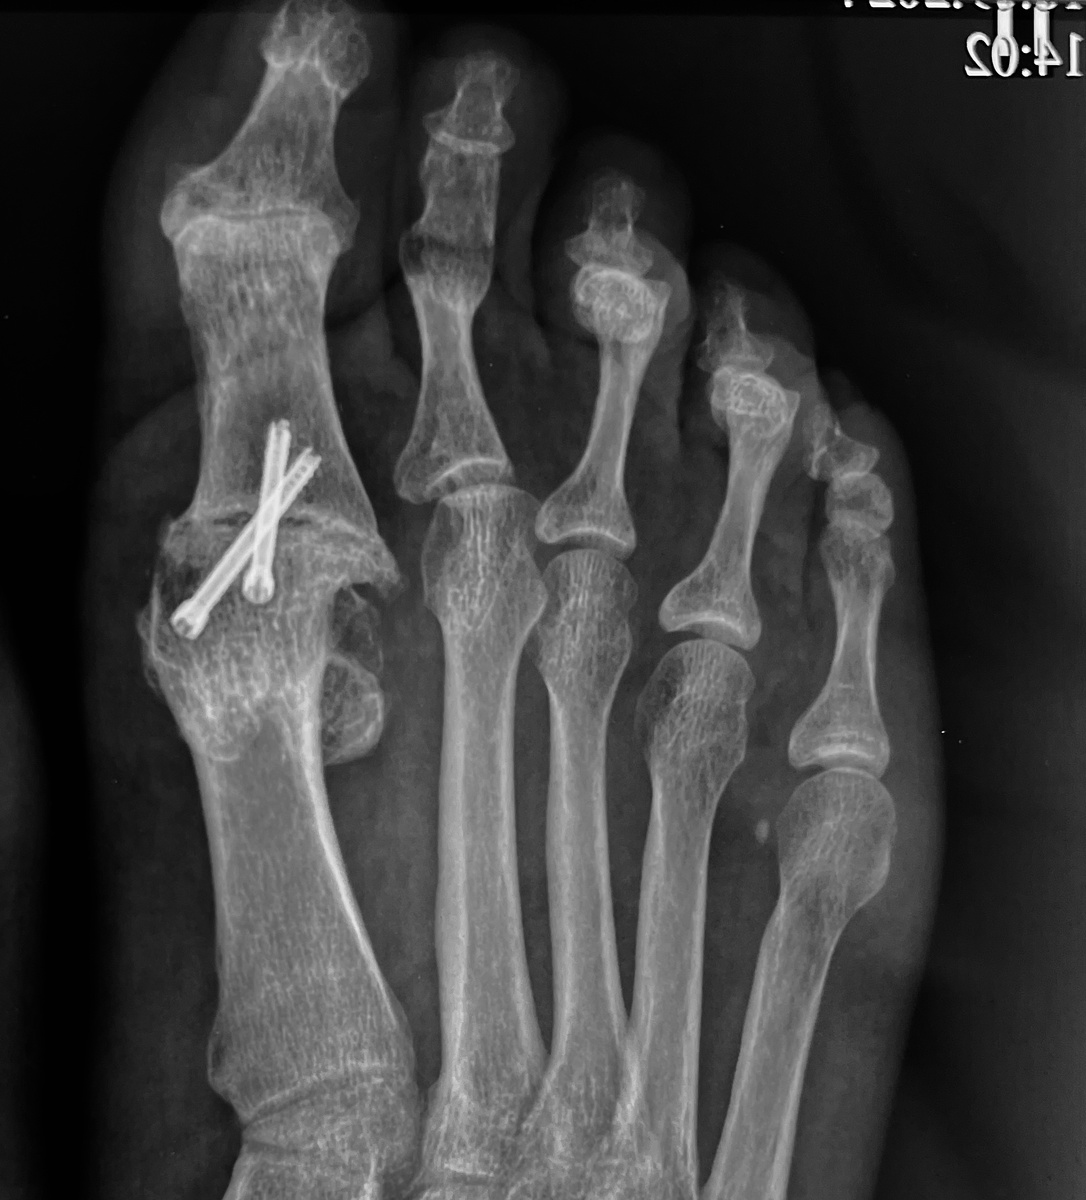

С учетом того факта, что с возрастом запросы в отношении обуви снижаются, и многие просто переходят на ношение ботинок а ля «прощай, молодость», то до хирургического лечения частенько не доходит. А, если доходит, то в большинстве случаев, видя полностью или частично разрушенный сустав, хирурги просто делают артродез - блокируют сустав. Смысл операции состоит в удалении остатков суставных поверхностей костей, костно-хрящевых разрастаний, и соединении костей между собой. Кости постепенно срастаются, что избавляет человека от боли.

Сейчас расскажу историю пациентки, которой я в 2017 году заменил один коленный сустав в связи с артрозом. На тот момент артроз сустава большого пальца второй ноги уже был, но особо не беспокоил. Со временем он спрогрессировал (это неизбежно), поменялась походка, искривилась нога. Хирурги по месту жительства сделали артродез, заблокировали сустав. К сожалению, сделали это не совсем правильно: и не под нужным углом, и без коррекции продольного свода. Получилось вот так:

Здесь формально вроде и ничего…

А вот здесь совсем плохо…

По-хорошему, во время этой операции нужно было скорректировать продольный свод, и стабилизировать стопу в вертикальном положении, но этого не сделали. В результате очень сильно нарушилась походка, и даже замена правого коленного сустава ситуацию не поменяла.